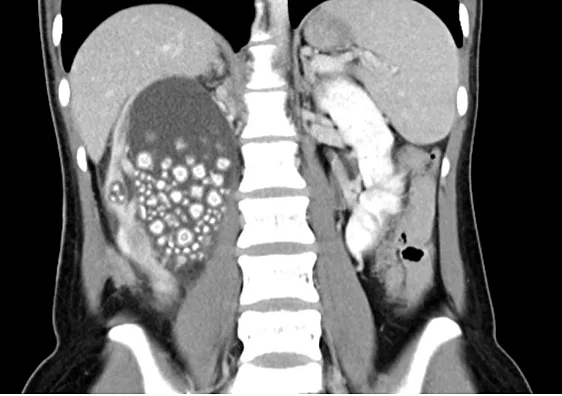

.שיאו צ'ו, צעירה בת 20 מטאיוואן, הרגישה כאבים עזים בגופה. במהלך בדיקה רפואית שלה התגלה כי הכליה הימנית שלה הייתה במצב קריטי כשהיא עמוסה בנוזל ועמוסה בצפיפות בכ-300 אבנים בכליות בגדול של 5 מ"מ ועד 2 ס"מ. מצבה של שיואו יו הסתבך עוד יותר בשל ספירת תאי דם לבנים גבוהה, מה שמעיד על זיהום.

הצוות הרפואי בבית החולים צ'י מי בטיינאן נקט פעולה מיידית. שיאו יו קיבלה אנטיביוטיקה כדי להתמודד עם הזיהום, ואחריה הליך לניקוז הנוזלים מכליה. השלב שהגיע לשיאו היה ניתוח לחילוץ האבנים הרבות.